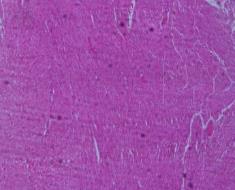

Microscopic examination of heart:

Sections show wall of heart composed predominantly of thick myocardium consists of bundles of cardiac muscle fibers separated by a fibrous band, forming a syncytium. Nuclei of myocytes are centrally located. The endocardium is lined by single layer of mesothelial cells resting on a basement membrane. No significant pathology is seen in any of the sections examined.

Fig. 1: Microscopic examination of male rabbit’s heart, stomach, liver and kidney tissues treated with S. nigra extract